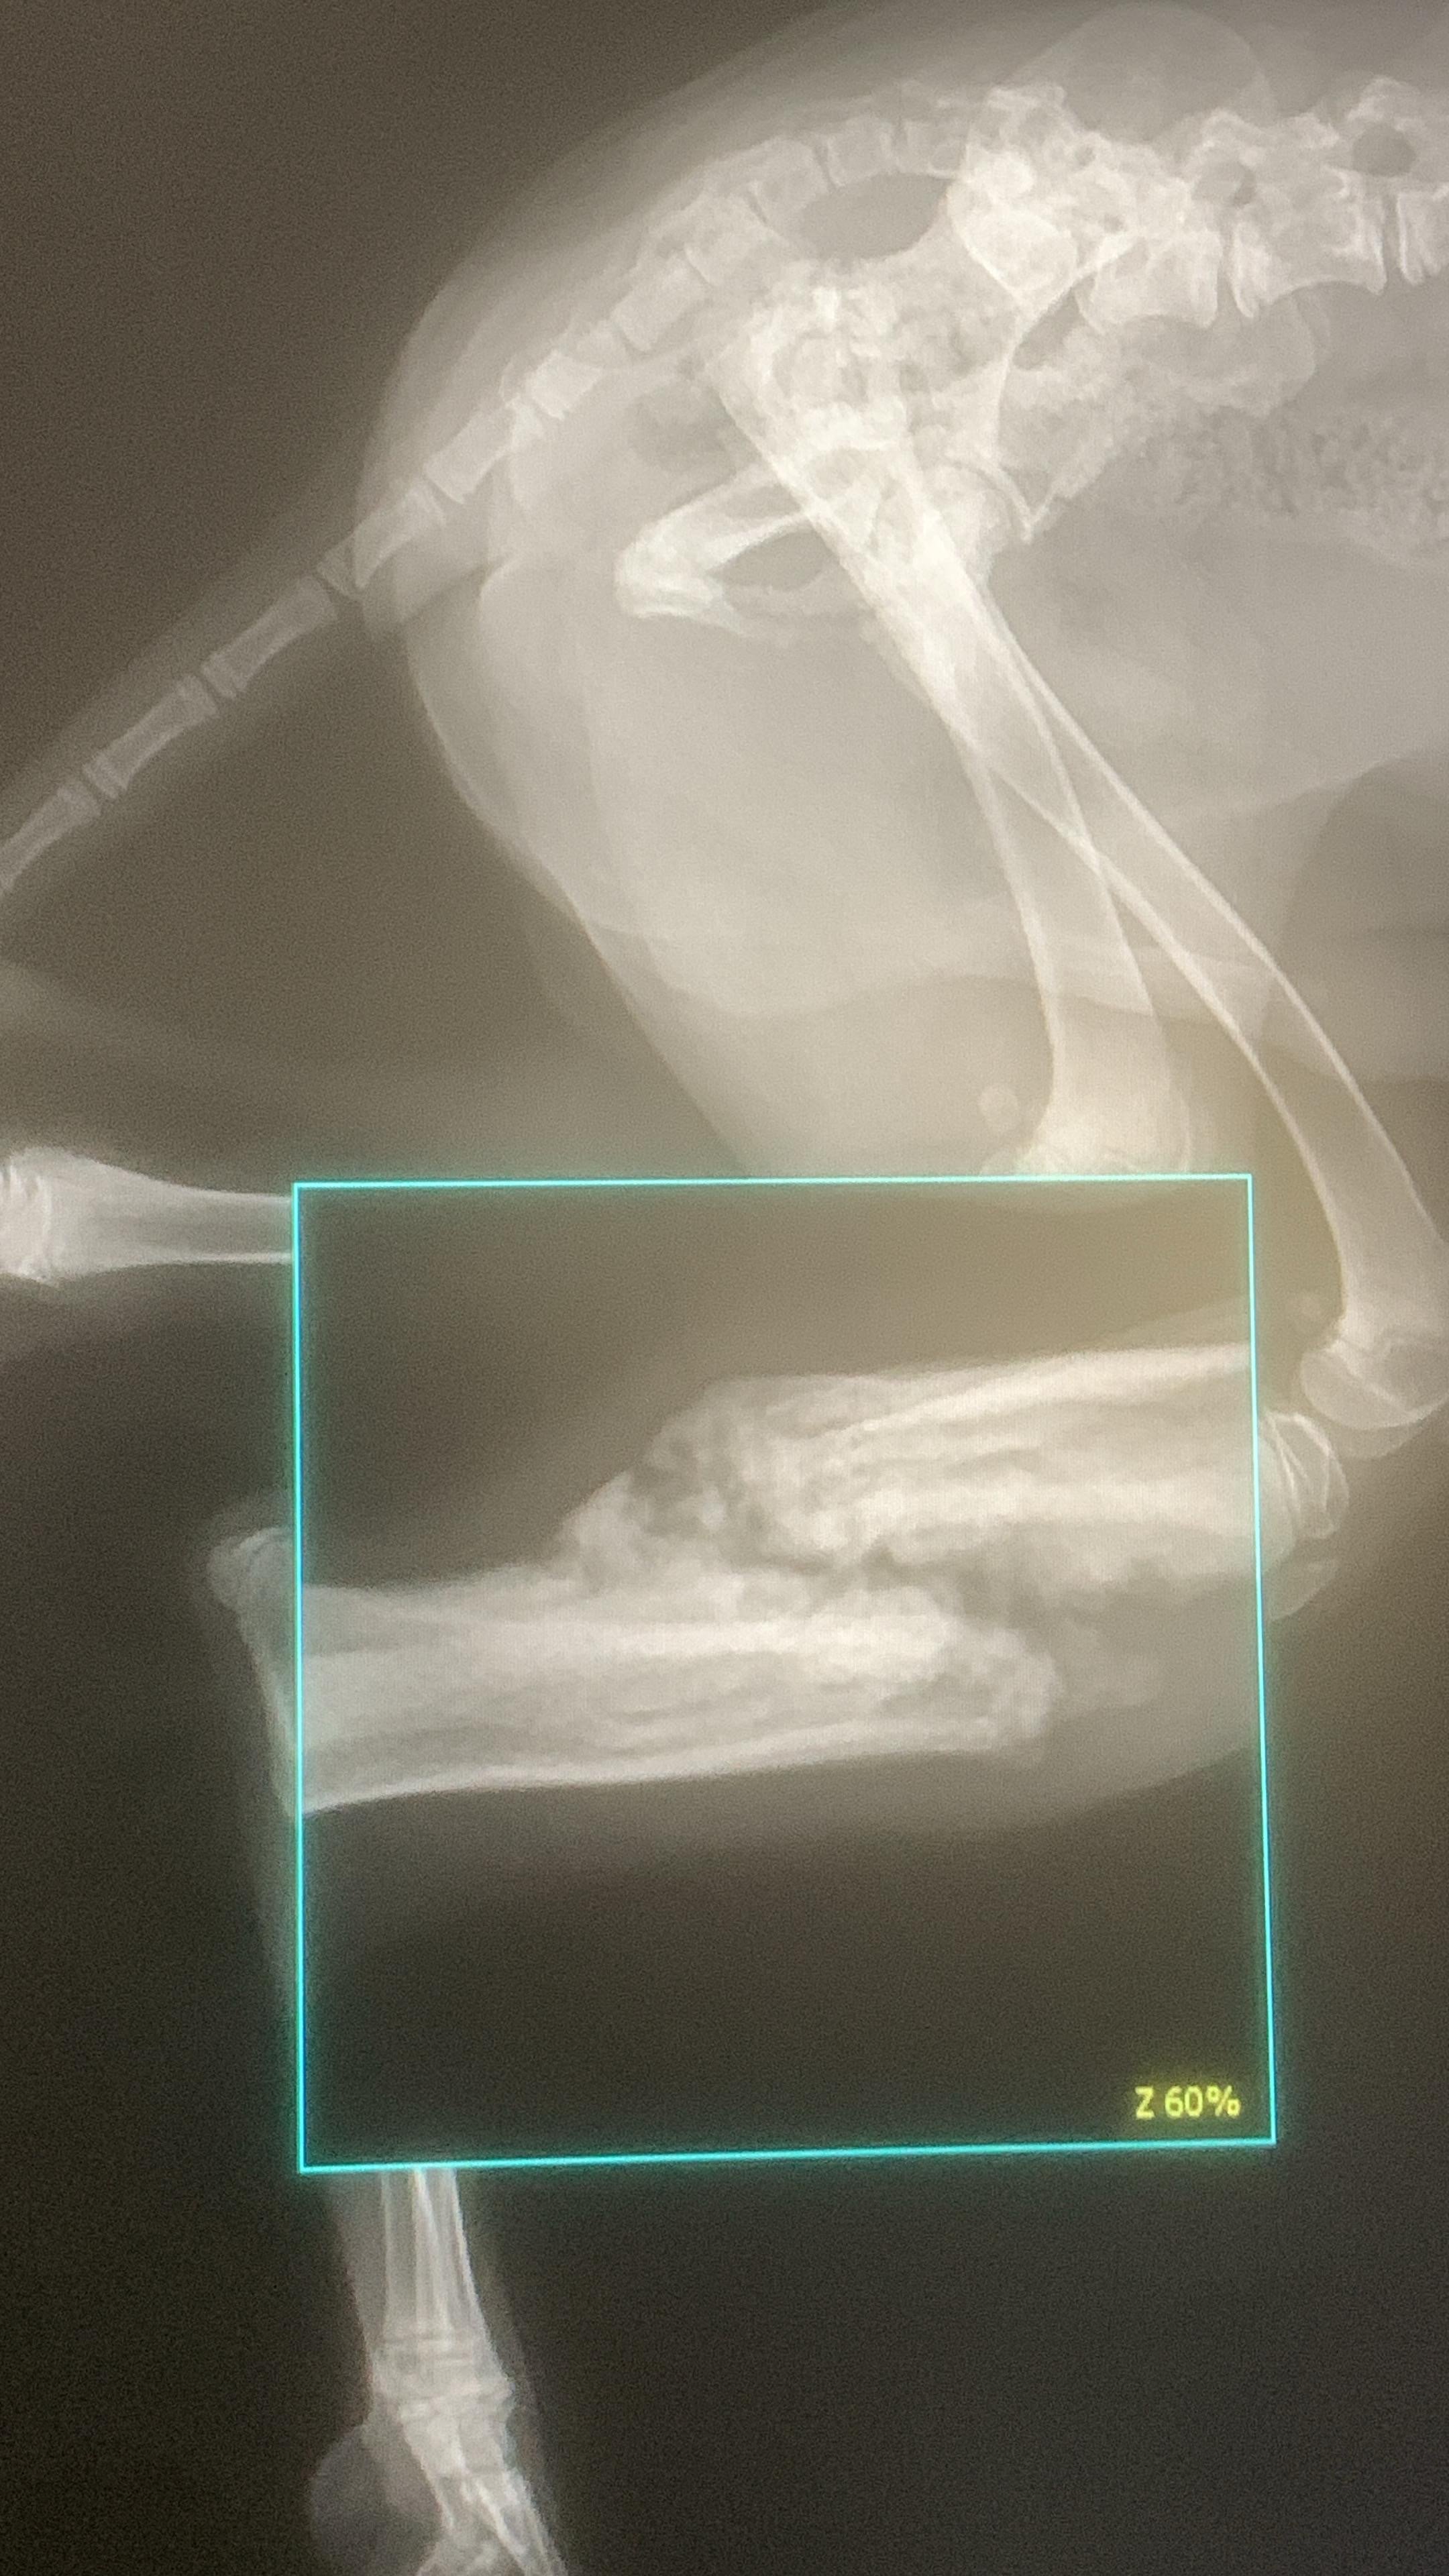

Nach einem zweiten Röntgen erklärte dieser Tierarzt, dass der Bruch von selbst verheilt sei.